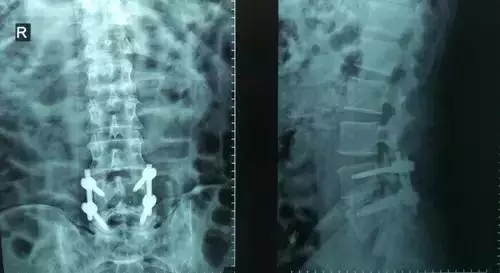

劉志安副院長所說的“微創(chuàng)小切口”就是通道下髓核摘除植骨融合經(jīng)皮內(nèi)固定術(shù)。其原理就是利用MIS-TLIF技術(shù)微創(chuàng)治療腰椎疾病,不但能達(dá)到開放手術(shù)的效果,且切口及創(chuàng)傷為開放切口的1/3,術(shù)中出血量少,患者術(shù)后可以恢復(fù)更快。

劉志安副院長將具體的手術(shù)過程向朱先生做了介紹,朱先生也同意了這個(gè)“微創(chuàng)小切口”手術(shù)。于是在術(shù)前的精心準(zhǔn)備之后,劉志安副院長協(xié)同其他醫(yī)護(hù)人員為朱先生進(jìn)行了手術(shù)。術(shù)后,朱先生的切口愈合良好,腰部疼痛消失,小腿麻木感也漸漸緩解。“手術(shù)后傷口略微有點(diǎn)痛,現(xiàn)在已經(jīng)完全不痛了,這種輕松的感覺已經(jīng)好久沒有了,真是萬分感謝劉院長。”在病房內(nèi),一臉笑容的朱先生如是說。

據(jù)劉院長介紹,MIS-TLIF技術(shù)是經(jīng)椎旁肌間隙入路運(yùn)用脊柱內(nèi)鏡或?qū)S猛ǖ佬醒甸g盤切除、椎管減壓、植骨內(nèi)固定術(shù),是一項(xiàng)應(yīng)用廣泛、技術(shù)成熟的脊柱微創(chuàng)手術(shù)方法。本技術(shù)可以完成與傳統(tǒng)手術(shù)完全相同的椎間盤切除、椎間植骨融合內(nèi)固定等操作。手術(shù)切口一般3-5厘米,本手術(shù)方式可有效避免傳統(tǒng)手術(shù)對腰背肌肉的損傷,患者術(shù)后腰背部疼痛輕、恢復(fù)快,手術(shù)效果優(yōu)于傳統(tǒng)手術(shù),治療后1-3天即可下床活動(dòng)。本技術(shù)適于大部分的腰椎間盤突出癥、腰椎管狹窄癥、腰椎滑脫癥等。